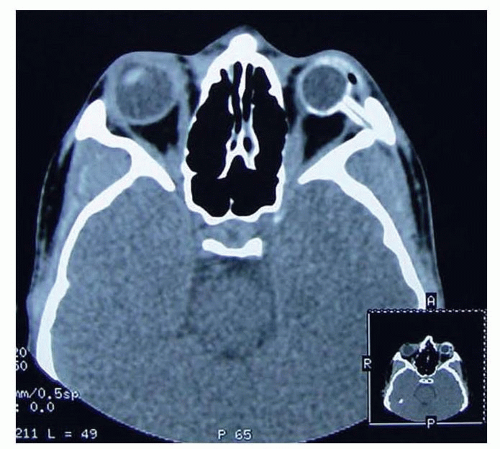

Computed tomography (CT) precisely delineates the bony anatomy but poorly defines the soft tissue structures and exposes the child to radiation. The implementation of lowdose radiation protocols has significantly lowered this theoretical risk (FIG 3).

FIG 3 • Follow-up CT scan showing the appropriate position of the intraorbital tissue expander.